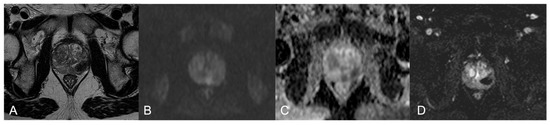

| 3 | PZ and TZ diffuse | Diffuse, inhomogeneous hypointensity, poor differentiation between PZ and TZ, glandular capsule preserved | Marked hyperintensity | Marked low ADC value | Inhomogeneous hyperenhancement, high peak | 5 |

| 4 | TZp mid-base right | 3.5-cm hypointense blurred nodule | Hyperintense | Marked low ADC value | Mild enhancement | 5 |

| 5 | PZpl mid-left; TZa mid-left | 2.8-cm hypointense area, capsular bulging; irregular, blurred marked hypointense TZ lesion | Hyperintense; hyperintense | Marked low ADC value; Marked low ADC value | Early and prolonged enhancement, high peak | 5; 5 |

| 7 | PZa right | 0.9-cm Hypointense nodule | Mild hyperintense | Low ADC value | Hyperenhancement | 4 |

| 9 | PZ diffuse | Blurred and confluent mild hypointense areas | Hyperintense | Low ADC value | Scarce enhancement | 4 |

| 10 | PZpm right | 1.3-cm mild hypointense nodule | Hyperintense | Low ADC value | Early enhancement, high peak | 4 |

| 11 | PZpm mid-left | Hypointense nodule | Mild hyperintense | Low ADC value | High and early enhancement, high peak, early wash-out | 4 |